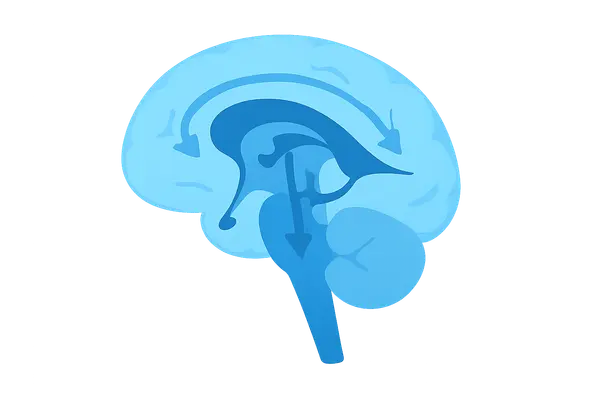

- Production: Choroid plexus in lateral, third, & fourth ventricles. Rate: ~20 mL/hr (~500 mL/day). Total volume: 90-150 mL.

- 📌 Mnemonic: "Love My 3 Silly 4 Lorn Magpies" → Lateral vents → Monro → 3rd vent → Sylvian aqueduct → 4th vent → Luschka → Magendie.

- Cerebrospinal fluid (CSF) is produced by the choroid plexus in the ventricles.

- Flows from lateral → third → fourth ventricles and exits via foramina of Luschka (lateral) & Magendie (medial).

- Arachnoid granulations are the primary site of CSF reabsorption into the dural venous sinuses.